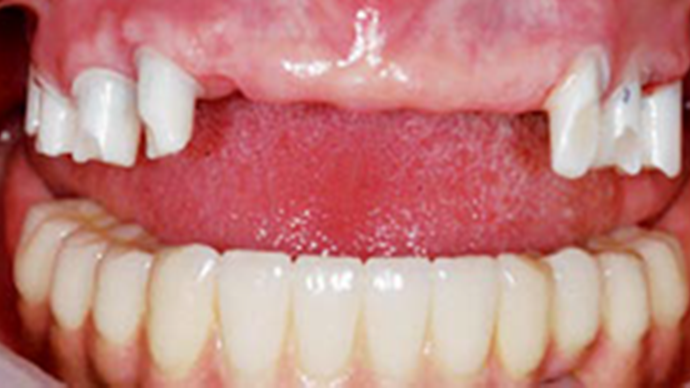

Clinical case: A Full transition from natural teeth to all-on-6 bridges

with AnyRidge implants

- Courtesy of Dr. Rabih Abi Nader, UAE -

Keywords

Full-mouth rehabilitation, minimal layering, Zirconia, all-on-6, life changing result, edentulous ,Dr. Rabih Abi Nader, AnyRidge

Products:

AnyRidge implant system